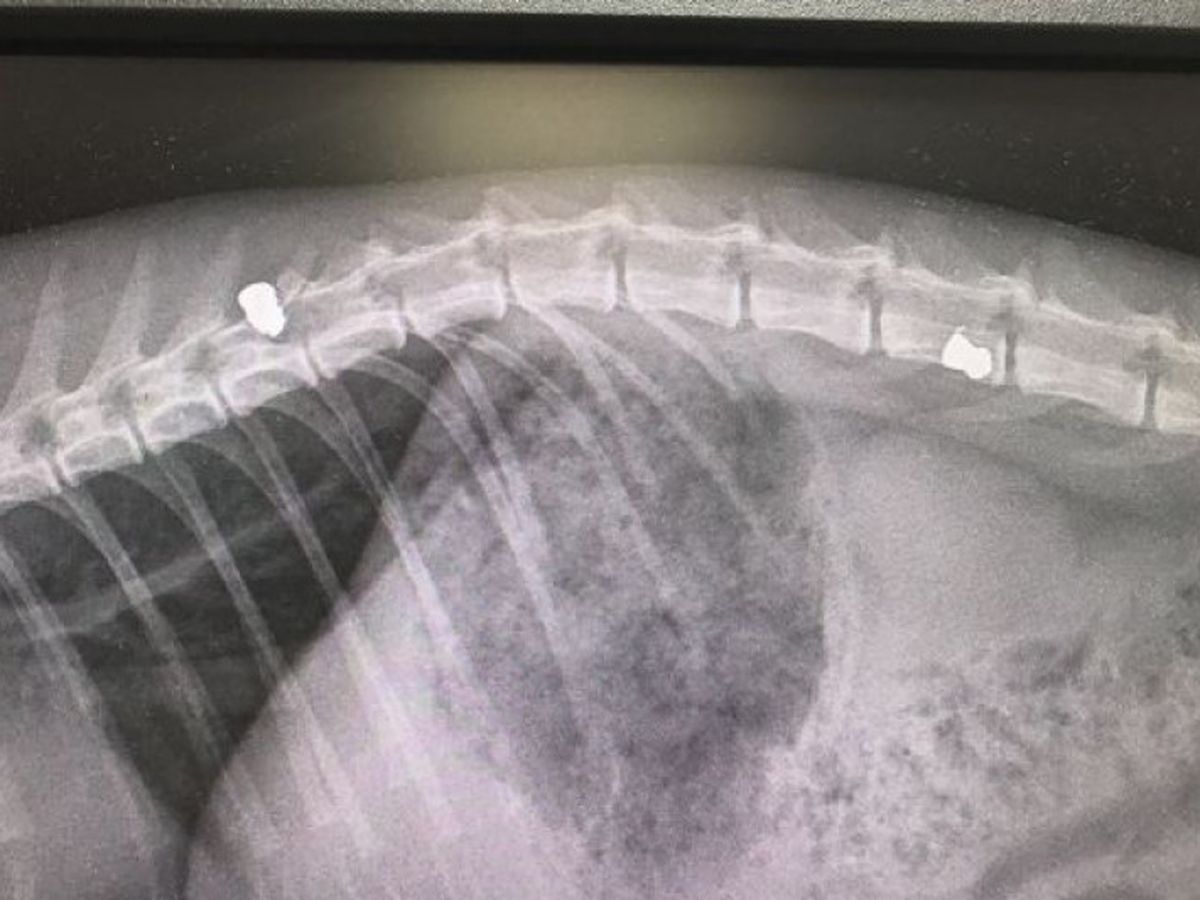

Queen B was callously shot 3 times with a pellet gun in her backyard in Saint Paul's, Bristol. She is only a year old and has also recently had kittens.

She has been paralysed and needs to see a specialist ASAP or will have to be put to sleep. Understandably, Queen B's owner Ali doesn't want to give up on her yet.